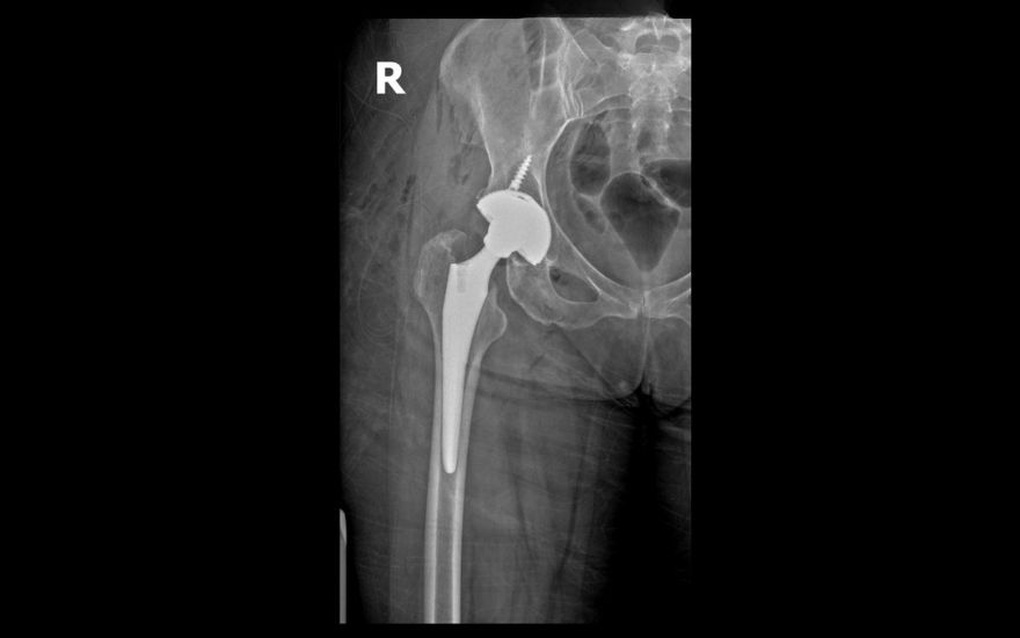

Phim chụp khớp háng của bệnh nhân Ronit sau phẫu thuật.

Tại BVĐK Hồng Ngọc – Phúc Trường Minh, bà Ronit được TS.BS Lê Quang Huy – Trưởng khoa Ngoại Chấn thương chỉnh hình – Thần kinh sọ não trực tiếp thăm khám. Sau khi đánh giá toàn diện các triệu chứng kết hợp cùng kết quả trên phim chụp X-quang, bác sĩ xác định bà bị gãy kín cổ xương đùi phải và cần phẫu thuật thay khớp háng toàn phần không xi măng sử dụng loại khớp hai chuyển động để giảm đau, khôi phục cấu trúc và chức năng vận động.

Sau hơn 1 giờ, ca phẫu thuật diễn ra thành công, phần cổ xương đùi bị gãy được thay thế bằng khớp nhân tạo có độ bền cao, chịu lực tốt, phù hợp cho bệnh nhân duy trì vận động lâu dài.